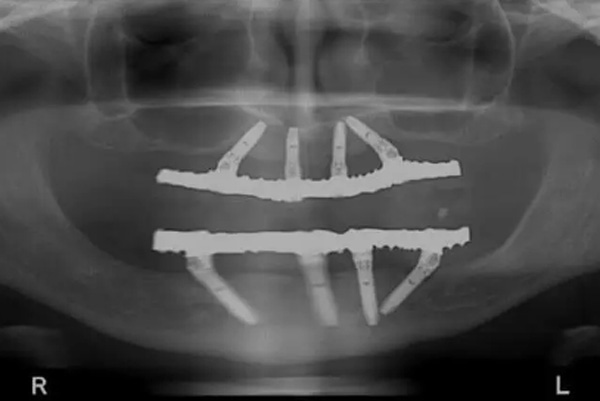

При методе All-on-4 в челюсть устанавливаются 4 имплантата, которые служат прочной опорой для фиксированного моста.

Имплантаты размещаются под специальными углами, чтобы:

- оптимально распределить жевательную нагрузку,

- максимально использовать имеющуюся кость,

- свести к минимуму объём хирургического вмешательства.

На эти имплантаты крепится мостовидная конструкция, на которую устанавливаются коронки — в итоге пациент получает полный ряд зубов «за один день».